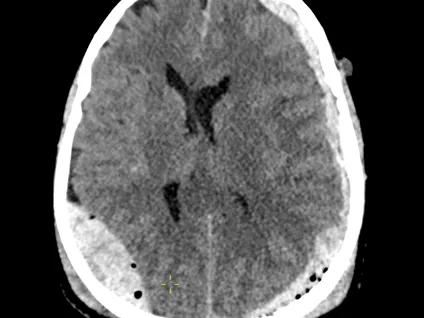

Traumatic brain injury is one of the most common causes of urgent imaging in busy emergency departments, therefore every radiologist must have confidence in reading trauma head CT studies.

This reporting module intends to promote a structural approach to reading traumatic brain studies, which makes it easier, and significantly increases sensitivity for more subtle injuries in otherwise near-normal studies.

The module will interactively demonstrate the common patterns of traumatic intracranial haemorrhages and the key points helping to differentiate them whenever possible. On the other hand, some cases were specifically selected to show the less common trauma-related findings, which are important to be aware of and not to overlook when reading the studies in your practice.

The training contains 5 anonymised CT cases from the TMC on-call department.